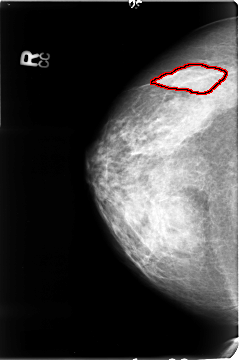

FILE: B_3048_1.RIGHT_CC.OVERLAY

TOTAL_ABNORMALITIES 1

ABNORMALITY 1

LESION_TYPE MASS SHAPE LOBULATED MARGINS CIRCUMSCRIBED-OBSCURED

ASSESSMENT 3

SUBTLETY 3

PATHOLOGY UNPROVEN

TOTAL_OUTLINES 1

BOUNDARY